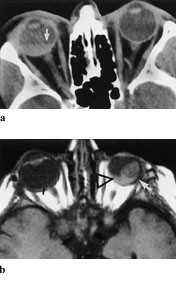

Melanomer gir karakteristisk signal fordi melanocyttene kan være paramagnetiske og gi høy signalintensitet på T1-vektede og lav signalintensitet på T2-vektede MR-bilder. Dette er karakteristisk, men mangler hos ca. 5 %. Postkontrast-T1-bilder med fettsuppresjon eller SPIR-teknikk er best egnet til å påvise små uveale melanomer (8) (fig 5).

Ekstraokulær utbredelse av uvealt melanom sees som et velavgrenset område med lav signalintensitet på T1-bilder, men med normal eller lav signalintensitet på T2-bilder i forhold til det orbitale fettet. Etter kontrast fremkommer bare moderat oppladning. MR er nyttig for å skille mellom en ekstraokulær ekspansjon og et ikke-oppladende fibrotisk arr i nær relasjon til sclera etter lokal stråleterapi.

Tåreveiene ble tidligere tradisjonelt fremstilt ved dacrocystografi, som er en invasiv teknikk og ofte krever sedering av pasienten. Senere er dette kombinert med CT, men nå kan spiral-CT med vannoppløselig kontrast gjøre undersøkelsen besværfri for pasienten (10). To dråper Omnipaque 180 gis i konjunktivalsekken hvert minutt i fem minutter. Så utføres spiral-CT-undersøkelse (fig 7). Dette gir en god fremstilling av tåreveiene, samtidig som det viser ansiktsskjelett og det omkringliggende vev i fine detaljer. Dette er utmerket metode både for øyeleger, øre-nese-hals-leger og plastikkirurger.